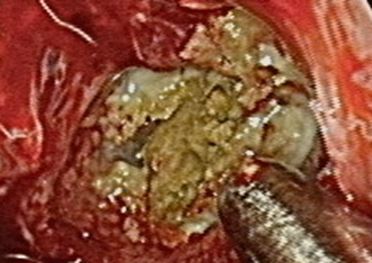

▲該男手術照片,黃色團塊為黴菌球。(圖/北市聯醫提供)

他進一步說明,經鼻竇內視鏡檢查後,發現該男左側鼻腔內有起士樣的膿鼻涕,進一步安排鼻竇電腦斷層顯示左側上頷竇內有不均質鈣化以及上頷竇外壁增厚情形,診斷為鼻竇黴菌球(Fungal ball)。

經討論後,患者決定接受內視鏡鼻竇手術。手術中順利將左側上頷竇開口擴大並將鼻竇黴菌球徹底清除。術後患者恢復良好,濃鼻涕與鼻塞情形大幅改善,腐臭魚腥味也從此消失了。